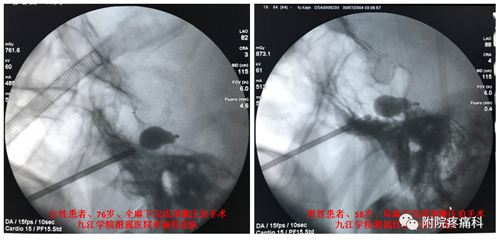

近日,临床医学院/附属医院疼痛科成功为多例顽固性三叉神经痛患者实行一种全新的微创手术——三叉神经球囊压迫术,这也标志着该院疼痛科熟练掌握该项技术并走在省内前沿。今后,九江及周边地区三叉神经痛患者不出远门,不开刀,仅通过面部一个针眼和数分钟操作,即可快速治愈、快速出院。

76岁的饶阿姨,右侧三叉神经痛有6年多。一开始用药物治疗效果明显,但随着时间推移,近来用药已达到最大治疗剂量,仍然不能控制疼痛发作。通过多方打听和比对,来到临床医学院/附属医院就医。行三叉神经球囊压迫术后,病症改善,效果良好,患者非常满意。她在出院时说:我原本准备今年去广州治疗的,患三叉神经痛多年,我对它也是非常了解,看起来切口不大,但头颅是人体的中枢机关,这并不是小手术;我从网上、病友那里了解了许多医院的多种治疗方法,早几年,能治这病的医院都不多,没想到现在我们附属医院就能治得这么好,我要把这里的技术和治疗效果告诉病友们,让他们早日解决痛苦!

三叉神经球囊压迫术手术方法简单,在X线透视监视下,将一个微球囊导入Meckle’s腔的三叉神经的半月节,然后缓慢注入对比造影剂充盈球囊,把导致三叉神经痛的神经纤维解除卡压、并通过扩张的微球囊压迫破坏,最后退出球囊,拔出穿刺针。术中病人耐受性良好,在全麻下接受整个手术,没有疼痛和不适感,伤口小(针眼大小), 手术时间短,术后疼痛立即缓解率可高达95%以上, 当天即可下床活动,基本不影响术后进食,并发症发生低。该手术适应症广,除了原有射频热凝术的适应症,对原发性三叉神经第一支疼痛、射频热凝术后效果欠佳的病人都有效,具有综合其它手术的优点:微创、安全、有效、风险小、不易复发。该手术因人性化、舒适度高、恢复快、病人接受度高,在欧美发达国家已广泛开展。